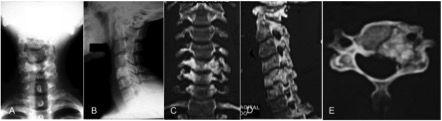

Osteosarcoma “tipo osteoblastoma” de columna cervical. A propósito de un caso. [Osteoblastoma like osteosarcoma of the cervical spine]